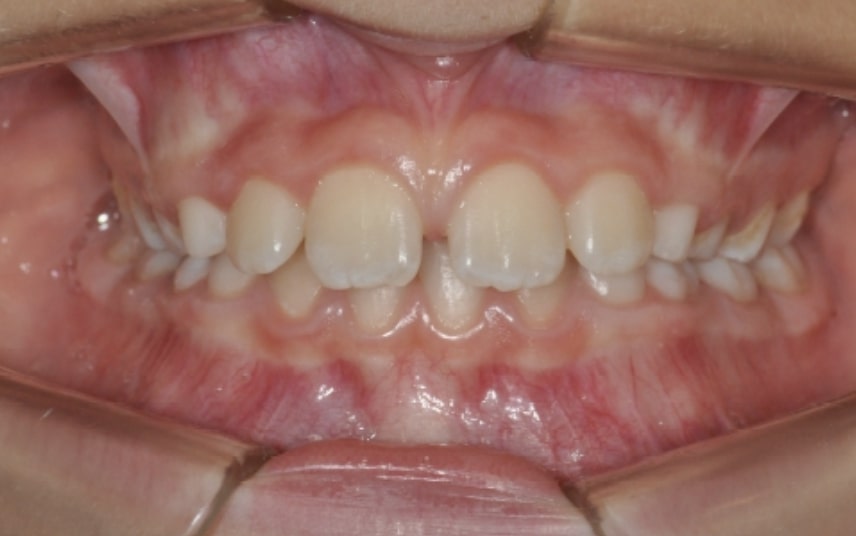

Malocclusion A6 Correction of Mandibular Retrusion in Growth phase patient | Skeletal Class II | Class II Division 1 malocclusion | Deep bite | Mixed dentition

Initial Photos and datas

Clinical examination and diagnosis

FUNCTIONAL: Suction of the lower lip and Labial incompetence.

FACIAL: class 2 profile with Lower jaw deficit

DENTAL:

• Molar and Canine class 2 on the right side – Molar and Canine clss 1 on the left side

• Upper diastema (11-21)

• Increased Overjet

• DeepBite

• Reduced Transversal Diameters

• Deviated Lower Midline 2 mm to the Right